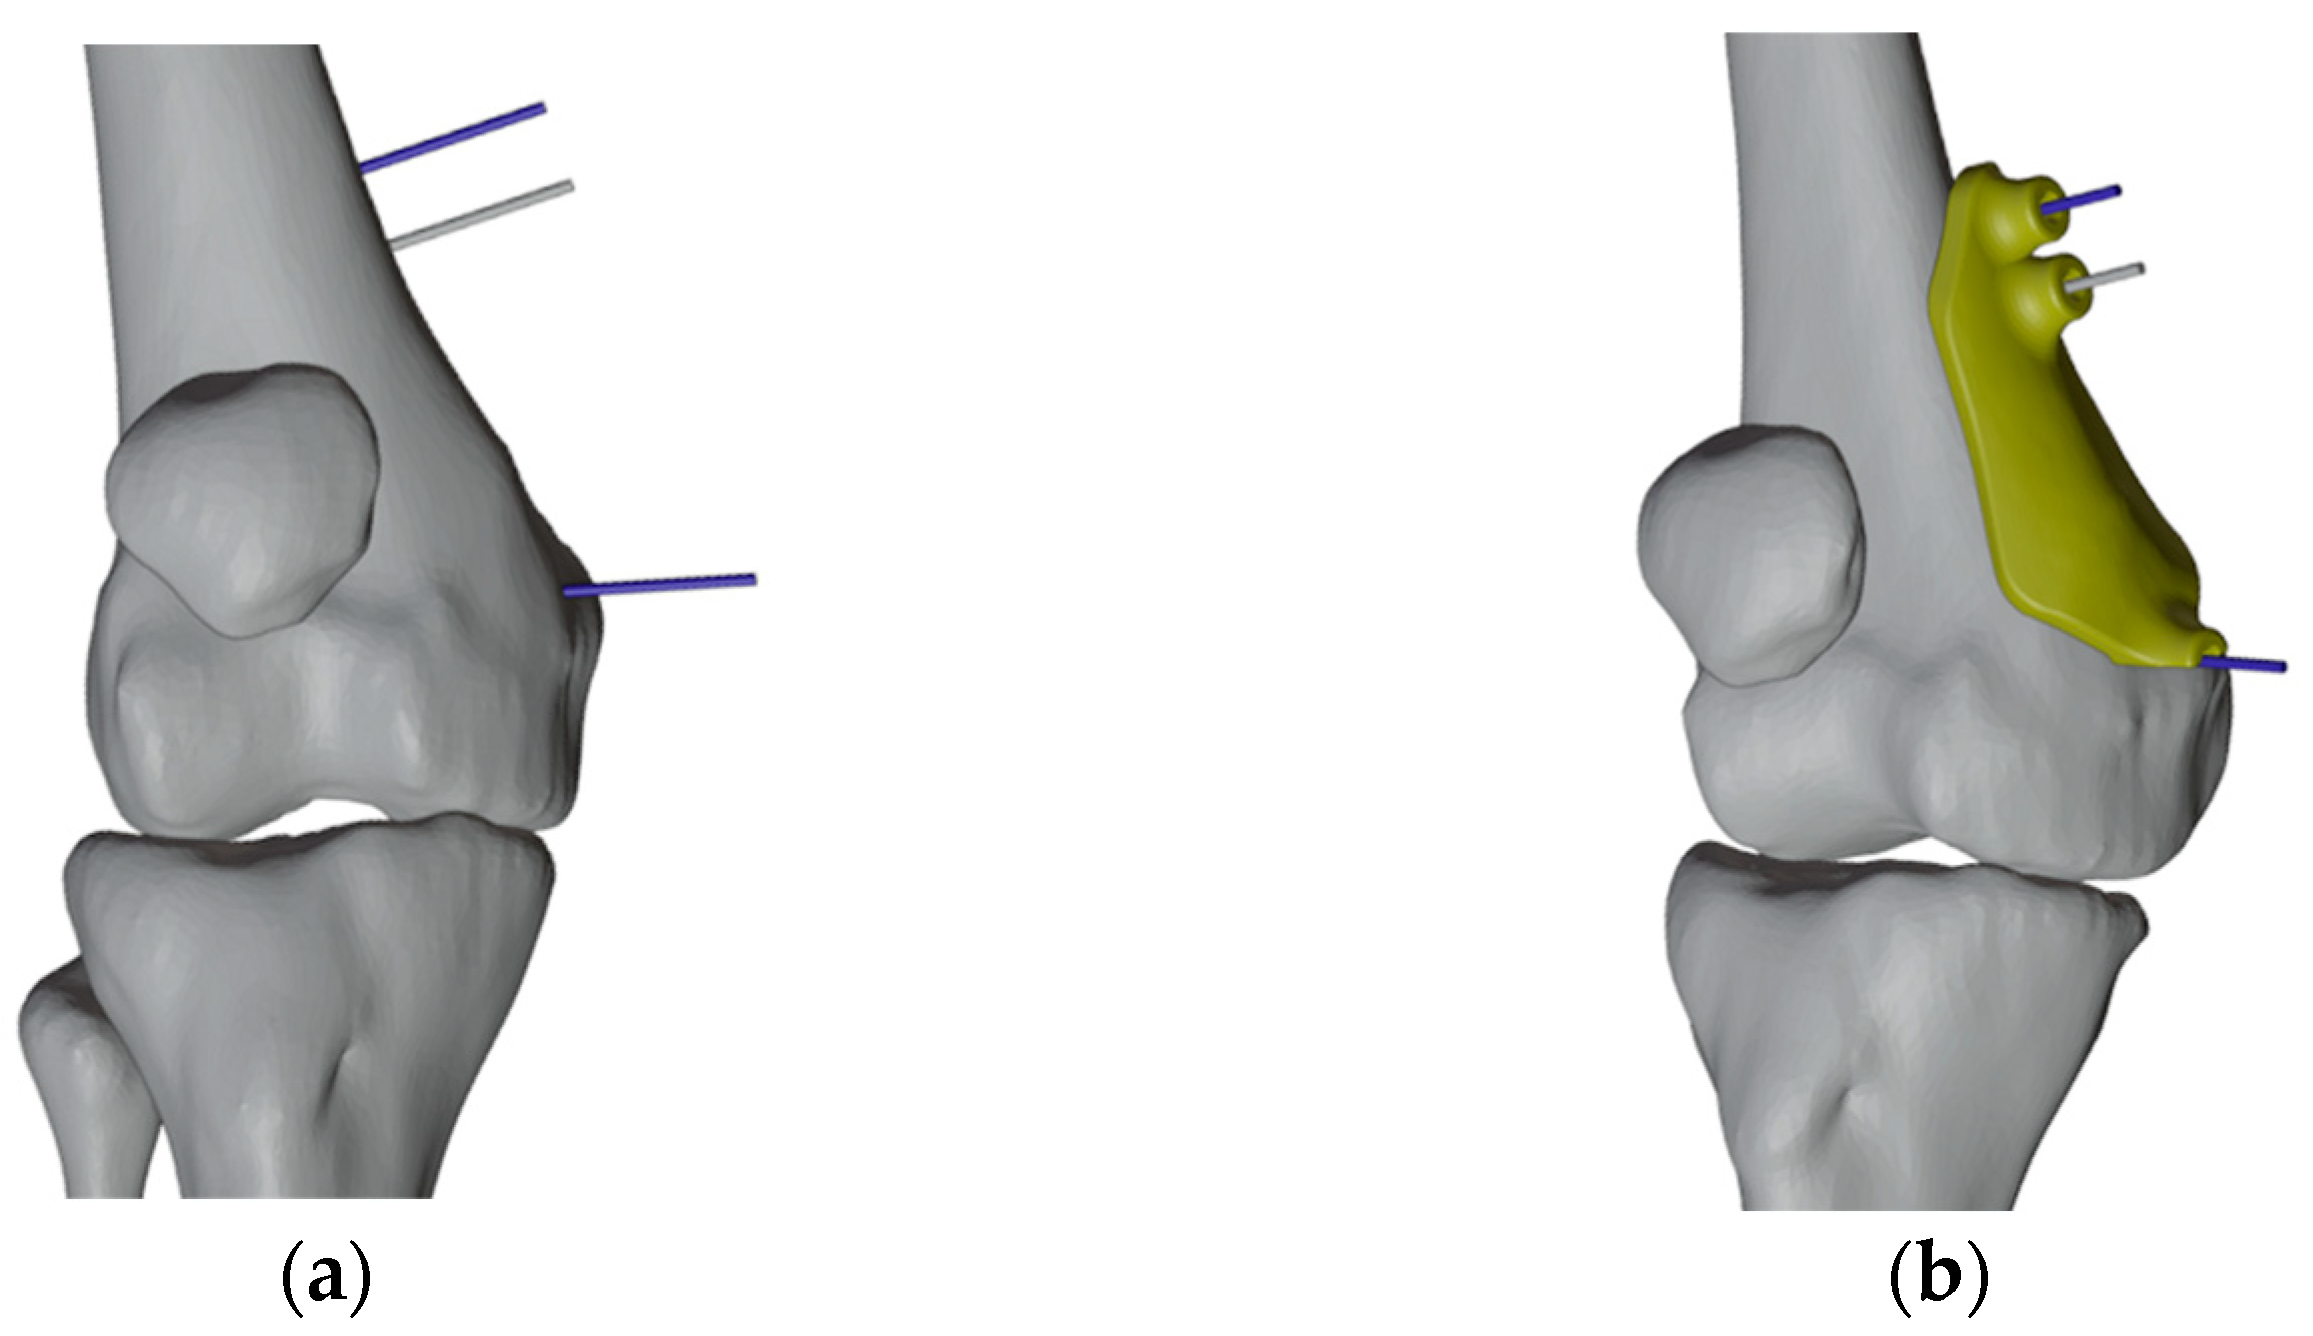

2.4. Design and Production of the Patient-Specific Instrumentation

2.4.1. PSIs Design for the Right Femur

2.4.2. PSI Design for the Left Femur